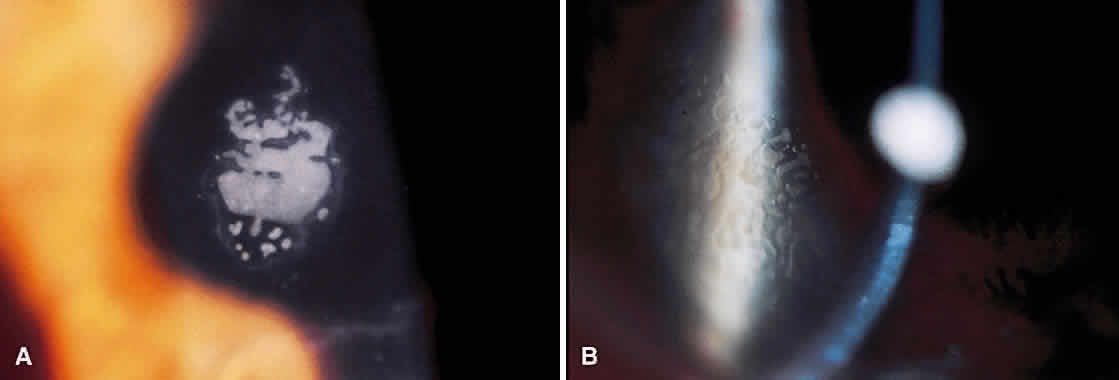

Corneal haze is a significant problem after PRK (Fig. 5). Although the vast majority of cases resolve and cause no visual sequelae, the possibility of regression and loss of BSCVA makes haze a great concern for PRK surgeons. The cause of the haze is likely an abundant proliferation of fibroblasts in response to the ablation performed. The grading of haze has been standardized in the literature (Table 3),98 with a grade of 2+ indicating clinical significance. Fortunately, the incidence of clinically significant haze after PRK is low, ranging from 0% to 6.7%.63 Several factors are thought to increase the likelihood of developing haze. The most important factor is the amount of attempted correction.99 Allergic conjunctivitis,100 when untreated, appears to be another important factor. However, keloid formers do not appear to have an increased risk of corneal haze.101

Fig. 5. Slit-lamp photographs of corneal haze after photorefractive keratectomy. A. Grade 1+ haze 3 months after surgery with minimal effect on best corrected visual acuity (20/25). B. Grade 2+ haze 4 months after surgery with significant decrease in best correct visual acuity (20/50).